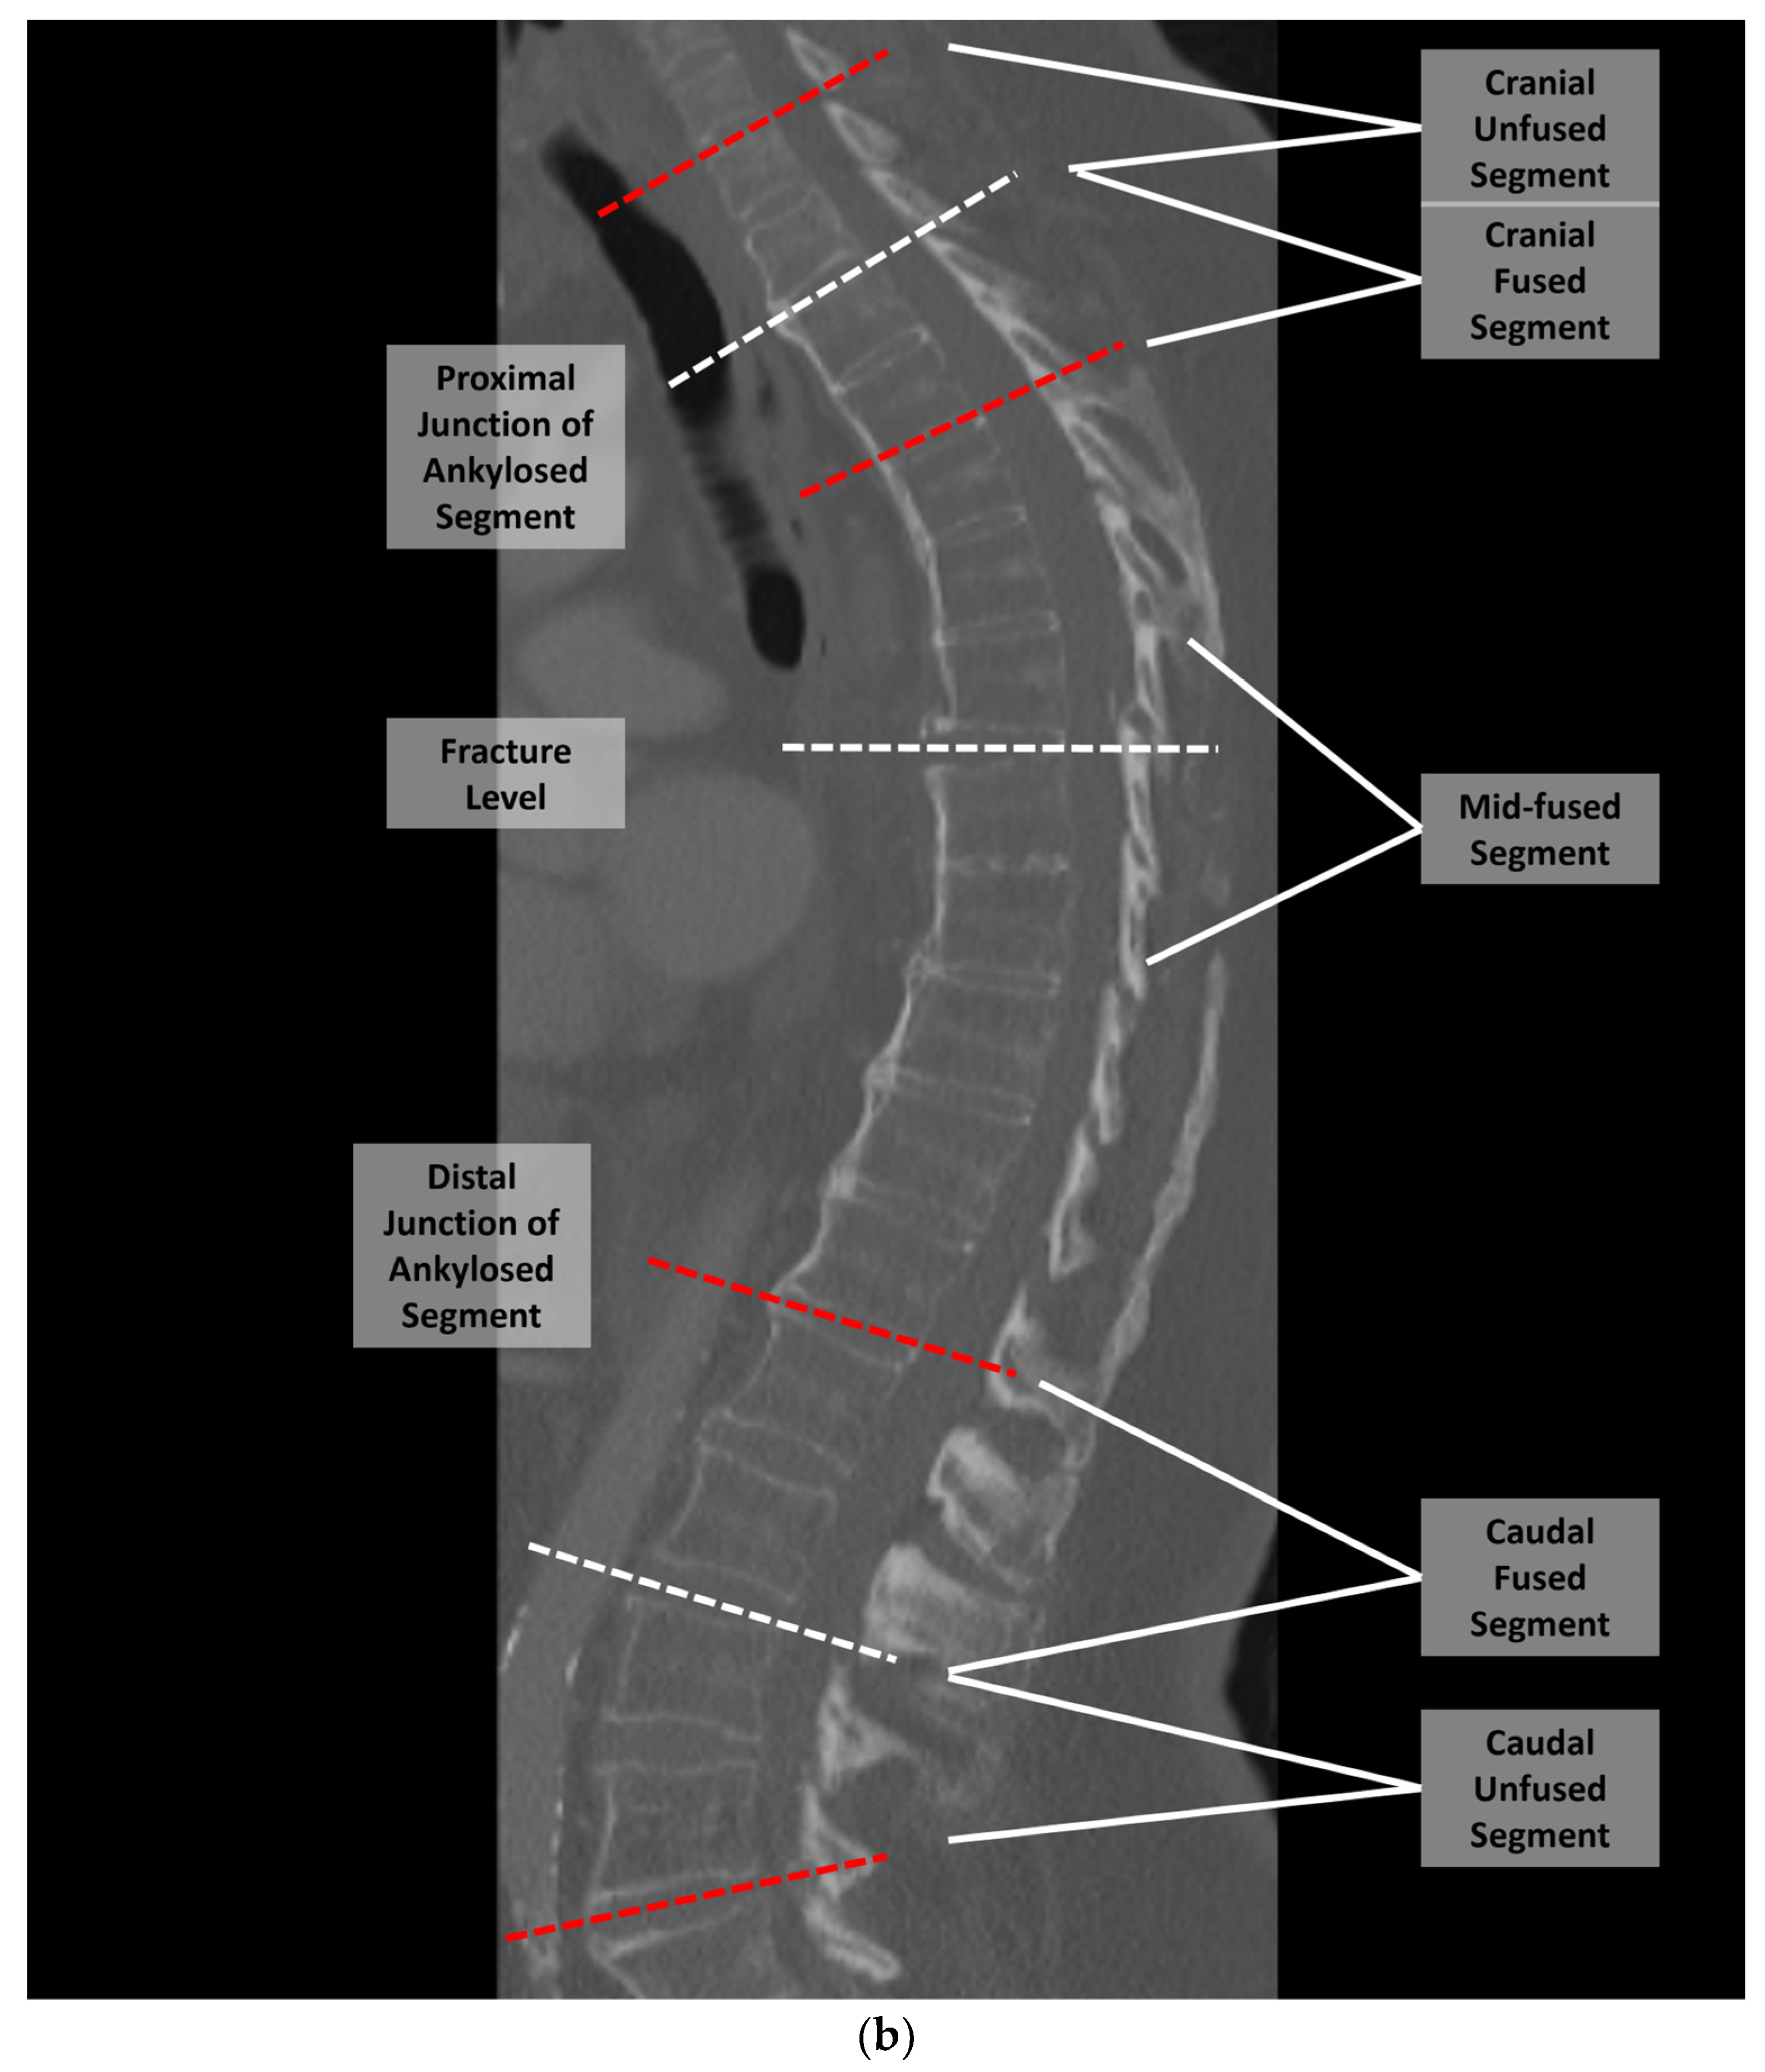

2. Materials and Methods